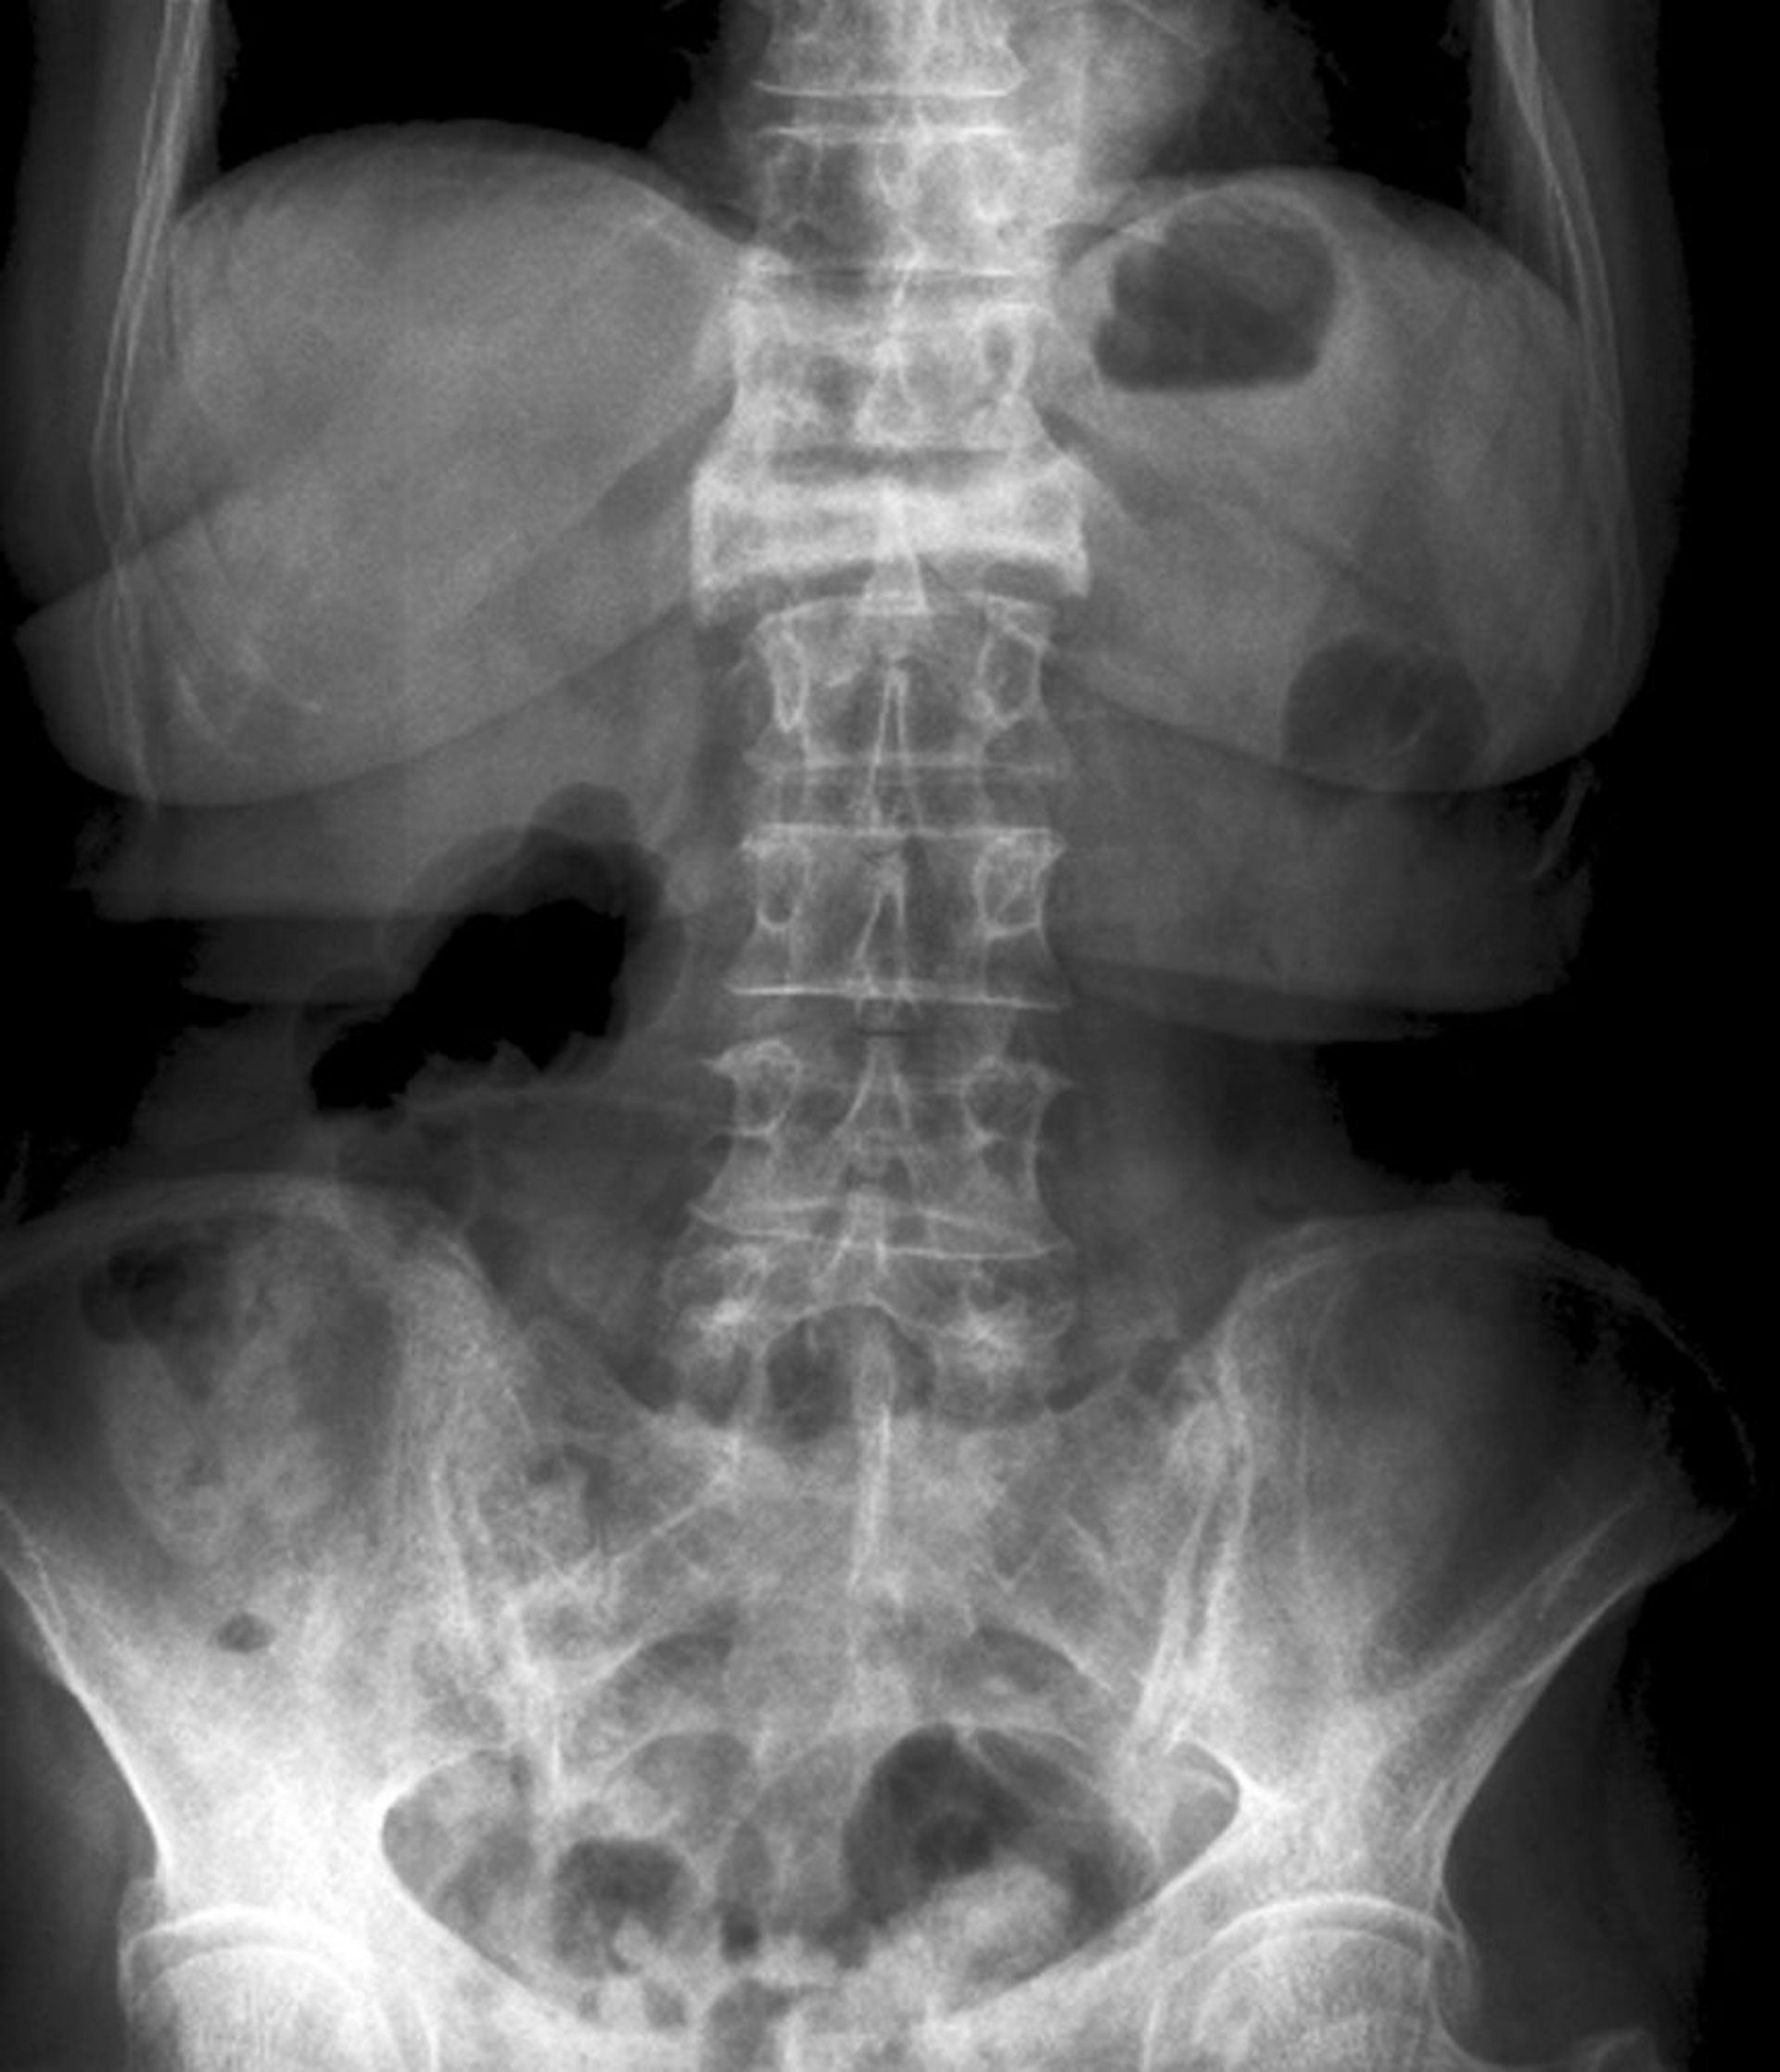

Anteroposteriore Ansicht einer schweren Kompressionsfraktur

Diese Kompressionsfraktur des 1. Lendenwirbels ist in der anteroposterioren Ansicht als starker Höhenverlust und erhöhte Radiodichte sichtbar.